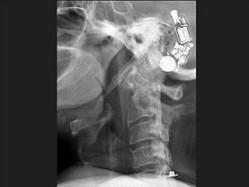

问题 女,58岁,颈部疼痛,活动受限,请结合图像,选出最可能的诊断 ( )

选项 A、椎间盘突出 B、局限性骨化性肌炎 C、颈椎结核 D、椎缘骨 E、颈椎退行性变

答案 E